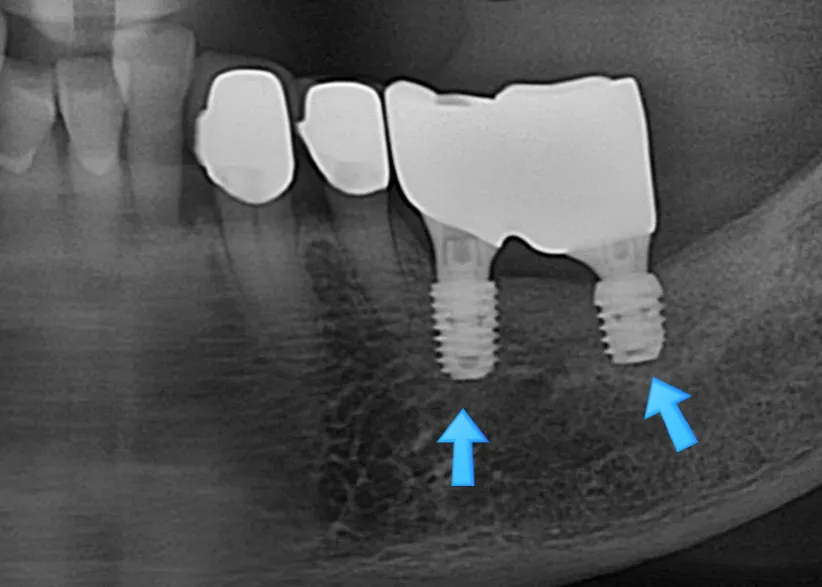

파노라마 X-ray — 파란색 화살표가 임플란트 주위염(Peri-implantitis) 부위를 가리킵니다

환자분의 엑스레이를 확인해 보니 ‘임플란트 주위염(Peri-implantitis)’이 심각하게 진행된 상태였습니다.

임플란트 주위염(Peri-implantitis)은 임플란트를 식립한 주변 조직에 염증이 생기는 상태로, 주된 원인은 치태(Dental Plaque)와 치석(Calculus) 같은 구강 내 세균입니다.

처음에는 단순히 잇몸의 염증으로 시작하지만, 좀 더 진행되어 임플란트의 거친 표면 티타늄 금속에 세균이 자리를 잡고 성장하는 순간부터는 보통 우리의 면역력이 세균을 이기지 못하고 100% 임플란트 뿌리까지 오염되게 됩니다.

이렇게 임플란트 주변의 뼈가 녹아버리면(골흡수, Bone Resorption) 기존 임플란트를 살려서 쓰는 것은 불가합니다. 게다가 같은 자리에 다시 임플란트를 심기에 아주 어려운 상황이 될 수 있는데요.